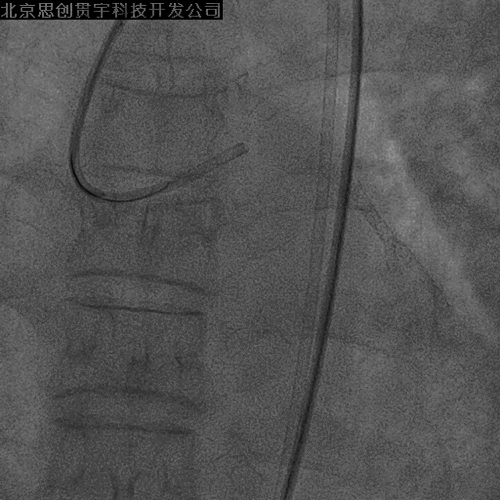

7F XB3.5指引; Pilot 150导丝;Finecross 130cm MG

LAD-IVUS

LAD中段既往支架膨胀不良

导丝主要位于真腔